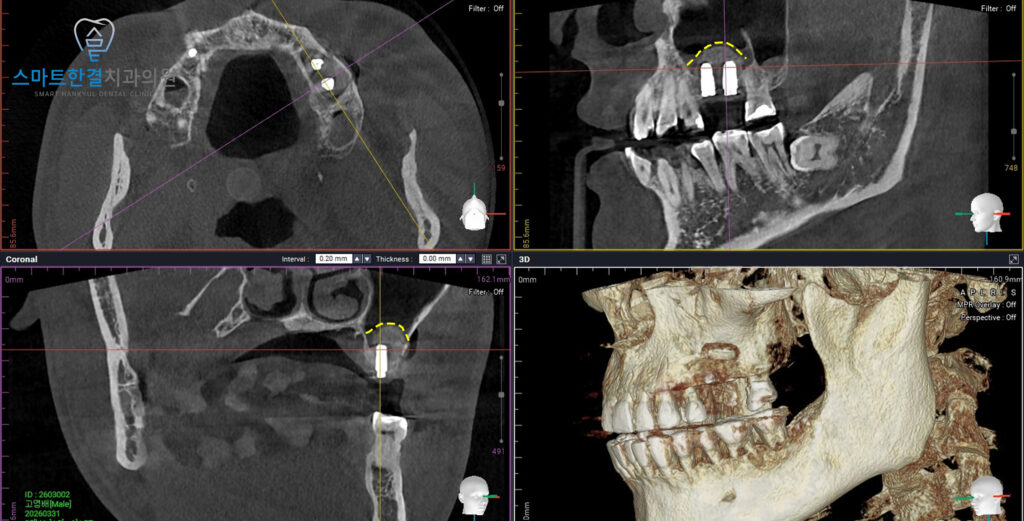

<CT 상에서도 확인되는 이식한 부분>

또한 CT를 촬영하여 확인해 보았을 때도,

특별한 이상 없이 상악동 거상술이

안정적으로 마무리된 것을 확인할 수 있었으며,

골이식된 부위 역시 계획한 범위 내에서

양호하게 형성되고 있는 상태였어요.

이처럼 정밀 진단을 통해

수술 후 경과까지 꼼꼼하게 확인함으로써

보다 안정적이고 예측 가능한 임플란트

치료 결과를 기대할 수 있으며,

환자분께서도 기능 회복 과정이

원활하게 진행되고 있음을 확인할 수 있었답니다!